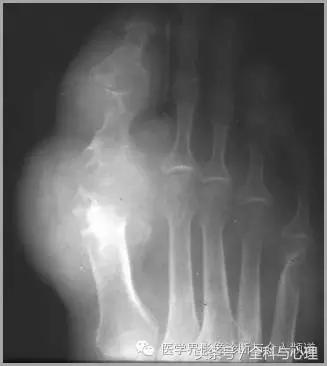

4、痛风石

为尿酸盐沉积形成,发生在关节周围软组织、包括韧带、肌腱、滑囊,眼、耳、鼻、喉、皮肤, 50%的钙化为X线平片可见。

软组织钙化与骨化,软组织钙化和骨质增生

痛风石,可见软组织肿胀及钙化灶。